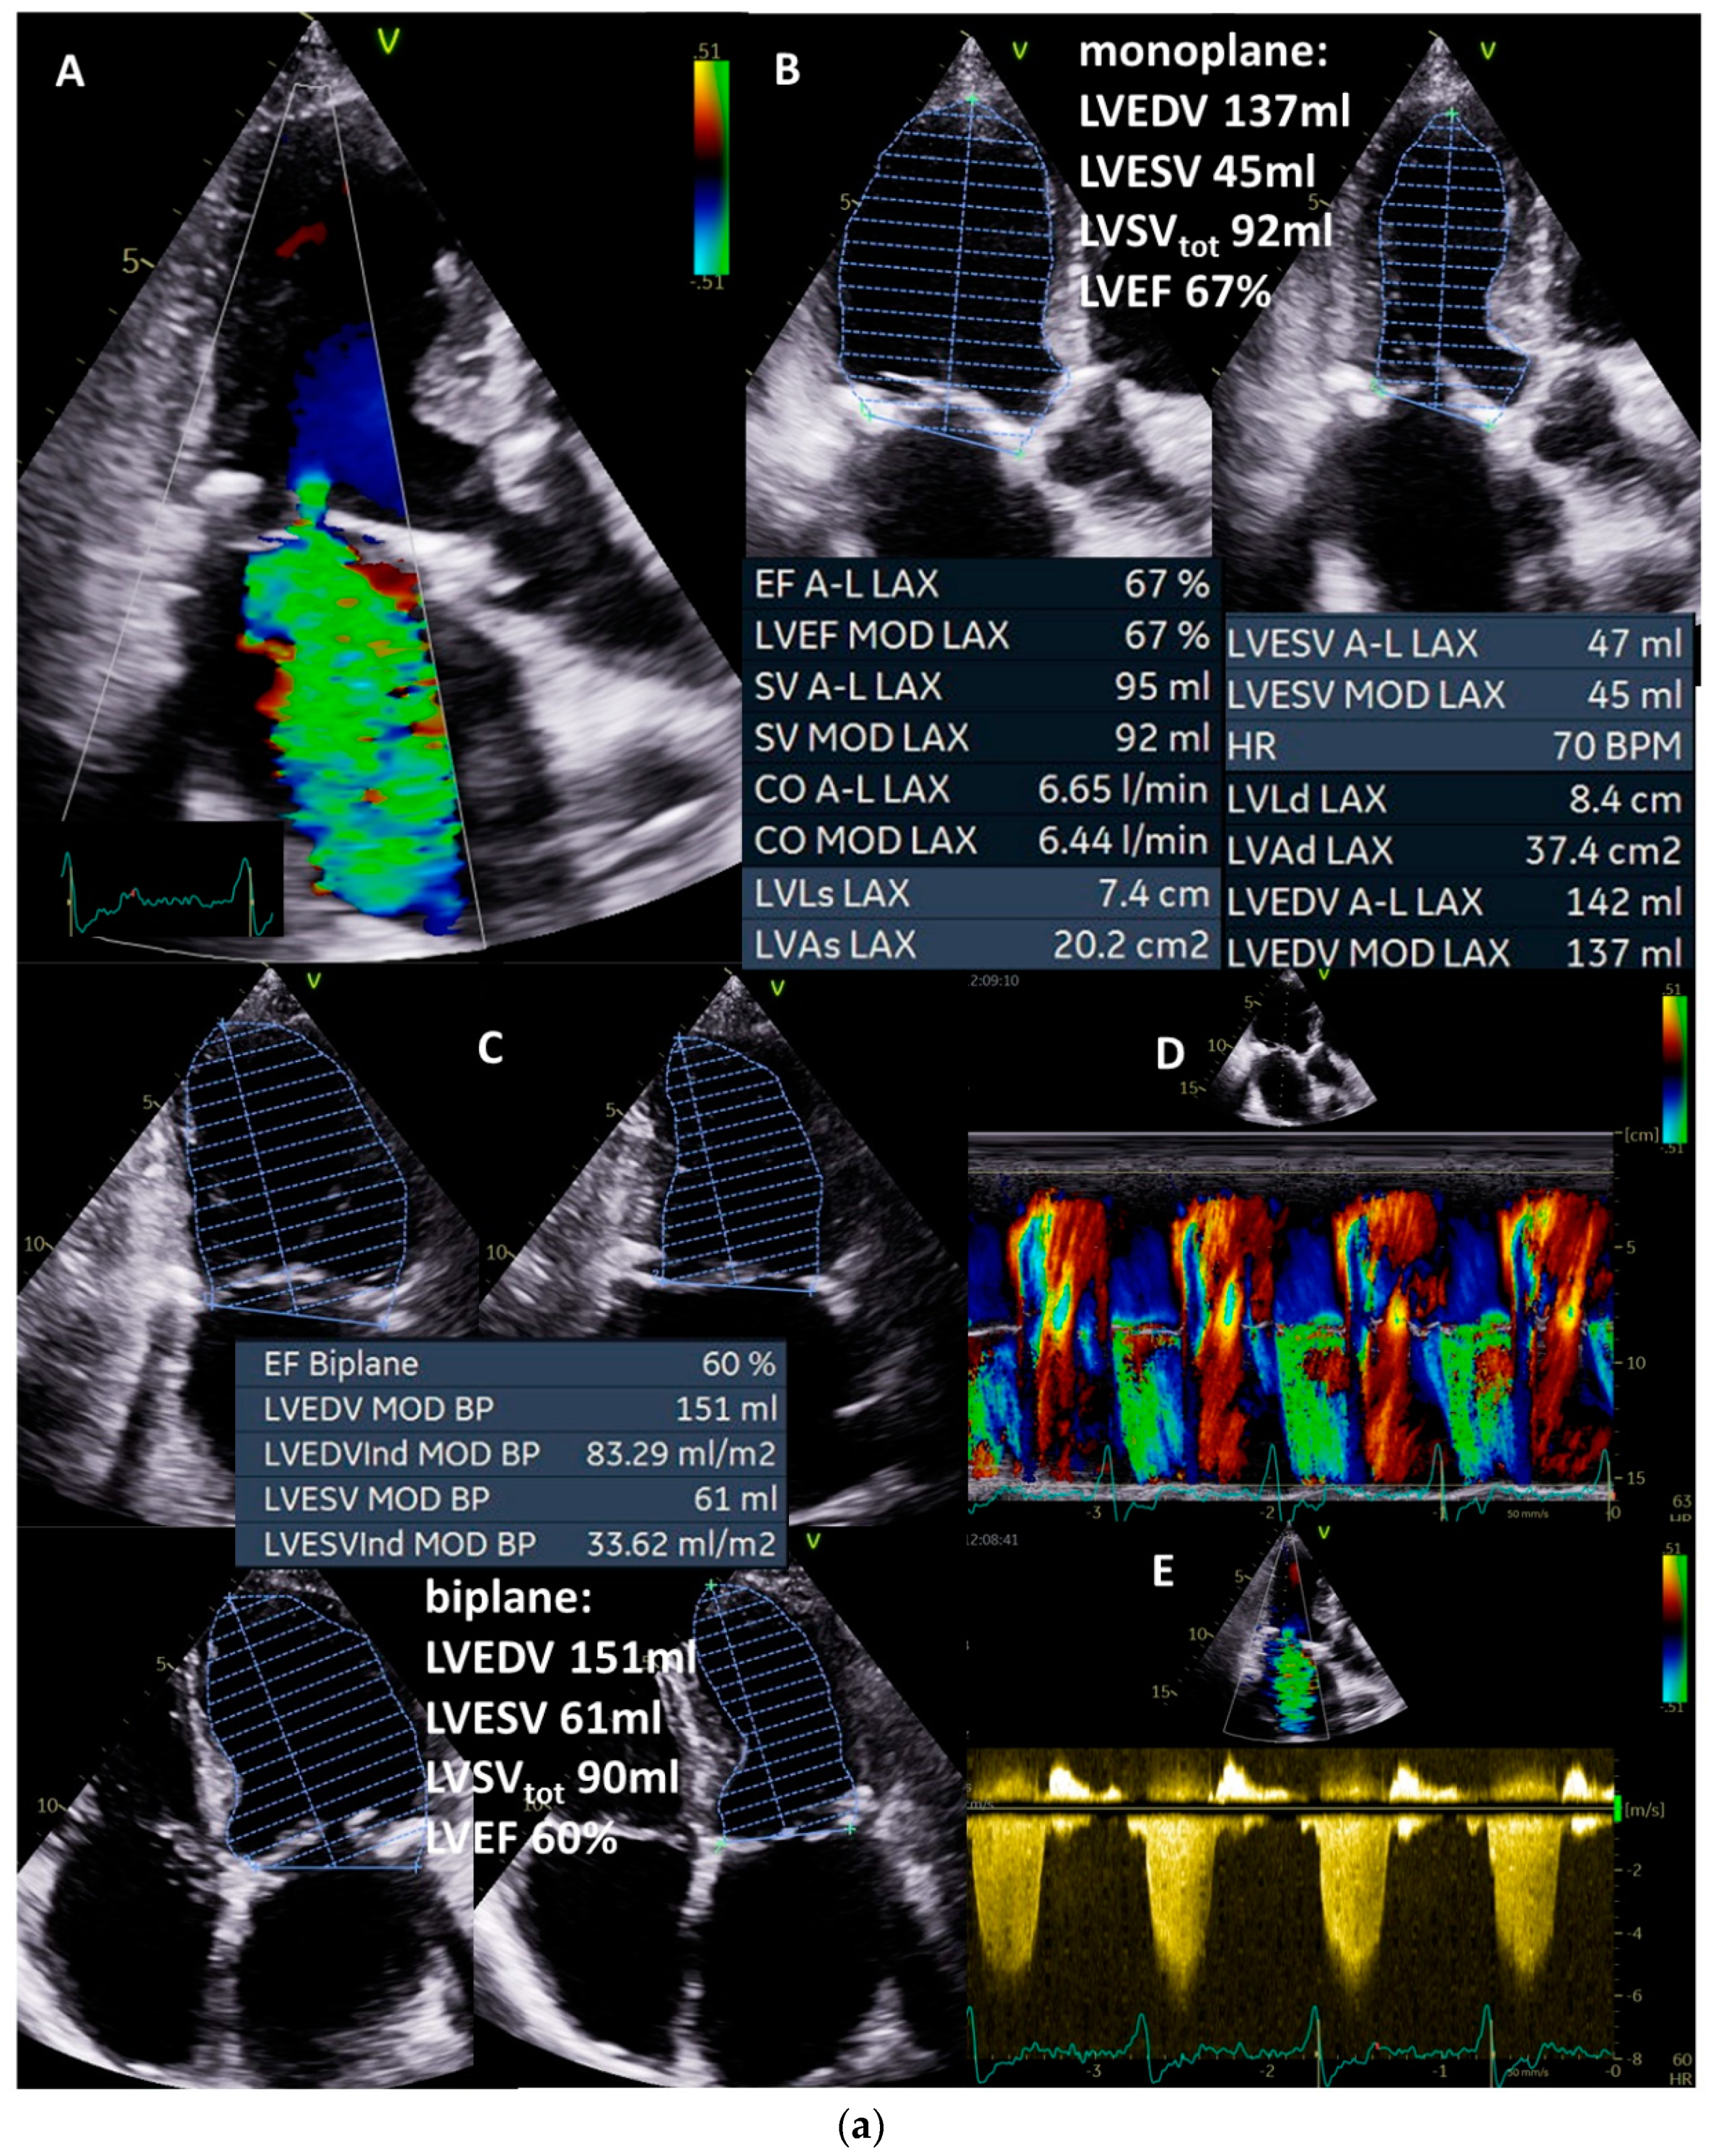

In the following case, a male 95-year-old asymptomatic patient (height: 172 cm, weight: 69 kg, BSA: 1.8 m2, blood pressure: 130/80 mmHg) with sinus rhythm presented to hospital because his daughter, herself a physician, was advised by a cardiologist to undergo interventional mitral valve therapy due to severe MR. The severity in terms of high-grade MR was based on eyeballing of the regurgitant jet area (Figure 2A and Figure 4a(A)) although, e.g., vena contracta is very small and the size of the jet area is not recommended to quantify MR severity [3]. Further, MR should be qualitatively documented and the etiology of MR—in this case, a secondary MR—must be diagnosed. Concomitant valvular defects were excluded, resulting in isolated MR. Ultimately, LVEDV, LVESV, LVEF, and total LVSV must be plausibly determined (Figure 4a(B)—monoplane, Figure 4a(C)—biplane). LVEDV was approximately 150 mL (within normal ranges), LVEF was approximately 60% (within normal ranges), and total LVSV was approximately 90 mL. Normal LVEDV and LVEF already indicate irrelevant MR.

Figure 4.

(a): Illustration of a systolic regurgitant jet phenomenon in a patient with isolated mitral regurgitation and the quantitative analysis of left ventricular volume parameters. In (A), the small vena contracta < 1 mm despite a remarkable jet area is shown. In (B), monoplane LV planimetry is shown using the apical long-axis view. In (C), the biplane LV planimetry is shown documenting a total LVSV of 90 mL. In (D), a color-coded M-Mode through the MR shows a nearly constant PISA radius. In (E), the cw regurgitant Doppler velocity is shown. LVEDV = left ventricular end diastolic volume, LVESV = left ventricular end systolic volume, LVSV = left ventricular stroke volume, LVSVtot = total LVSV, and LVEF = left ventricular ejection fraction. (b): Illustration to assess quantitatively effective LVSV and RVSV by pw Doppler echocardiography as well as regurgitant volume by 2D PISA method to analyze severity of mitral regurgitation (MR): in (A), the parasternal long-axis to document LVOT diameter during systole is shown; in (B), the measurements of LVSVeff by pw Doppler spectrum at the level of the LVOT is shown; in (C), the parasternal and subcostal short-axis views are shown to document RVOT diameter during systole; in (D), the measurements of RVSVeff by pw Doppler spectrum at the level of the RVOT is shown. The estimation of RegVolMR by 2D PISA is demonstrated by delineation of the 2D-PISA radius and the velocity time integral of the retrograde transmitral velocity during systole (E,F). LVSV = left ventricular stroke volume, LVEF = left ventricular ejection fraction, LVSVeff = effective LVSV, RegVol = transmitral regurgitant volume, LVOT = left ventricular outflow tract, RVOT = right ventricular outflow tract.

At this point in the examination, the findings should be checked for hemodynamic plausibility. Calculating the minimum effective LVSV to enable a required effective CO and CI at a heart rate of 63/min (corresponding to values of approximately CO = 4 L/min; CI = 2.2 L/min m2: 4000 mL/min/63/min = 63 mL) facilitates the interpretation. Thus, the maximum possible RegVolMR to be above shock limit is (90 mL − 63 mL = 27 mL), which corresponds to a RF of 30%.

Next, the effective LVSV should be quantified by Doppler echocardiography (Figure 4b(A,B)—pw-Doppler LVOT, Figure 4b(C,D)—pw-Doppler RVOT), yielding approximately 75 mL (Figure 4b(E,F)). Thus, RegVolMR was 15 mL in this case. RegVolMR can additionally be checked by 2D PISA method if there are no methodological limitations to the use of 2D PISA method (Figure 4a(D)—color-coded M-Mode—MR, Figure 4a(E)—cw-Doppler—MR, Figure 4b(E,F)—2D PISA method). Thus, RFMR was less than 20% in this case. In conclusion, secondary alterations, e.g., increased E/e’ ratio and/or increased systolic pulmonary arterial pressure, associated with relevant MR, should be considered to exclude high-grade MR.

In summary, this example documents mild functional MR confirmed by clinical presentation without symptoms, normal ranges of LVEDV and LVEF, and individual mild-grade RFMR < 20% at a calculated effective CO and CI of 4.7 L/min and 2.6 L/ min m2, respectively.